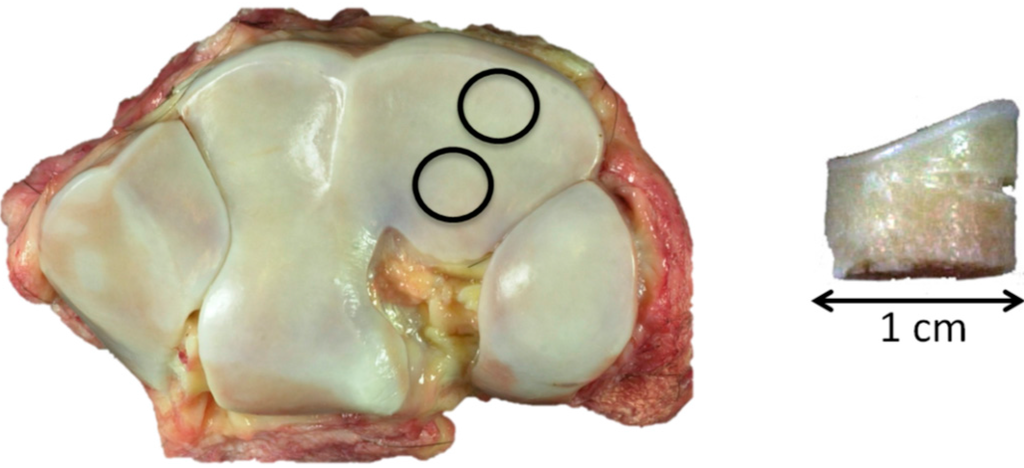

Tissue was harvested at a local abattoir from Standardbred racehorses with a previous racing career, as previously described [4]. A scoring system of the macroscopic cartilage degeneration in the third carpal bones was used to create control (C), early osteoarthritis (EOA) and advanced OA (AOA) groups. Briefly, control (C) specimens had no visible cartilage macroscopic lesions; EOA specimens had fissures and or partial thickness in an area less than one square centimeter or advanced osteoarthritis (AOA) with partial to full thickness erosions/ulcerations in an area greater than one square centimeter (Figure 6).

Figure 6. Third carpal bones, dorsal to top: Left, control; Center, early OA; and right, advanced OA.

Two 1-cm diameter osteochondral cores were harvested, one from the more dorsal common location for focal OA lesions in this bone and the second from a more palmar site that is rarely affected (Figure 7 left). The dorsal aspect of each core was notched for orientation (Figure 7 right).

Figure 7. Left, control, showing the 1-cm core sample location, dorsal top; and right, core sample with dorsal notch.